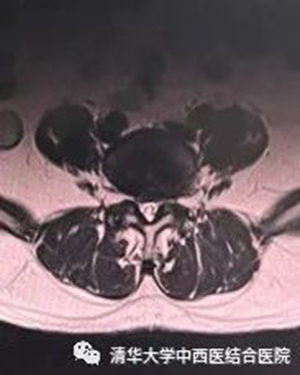

白色虛線代表腰椎椎體前后緣位置,黑色虛線為手術(shù)切口

如上圖所示,OLIF手術(shù)需要的切口很短,所以對(duì)軟組織肌肉的創(chuàng)傷較小,術(shù)后皮膚疤痕也很小。

如上圖所示,OLIF手術(shù)采用的椎間融合器體積更大,融合器內(nèi)植骨量也更多,所以椎體間融合率更高。